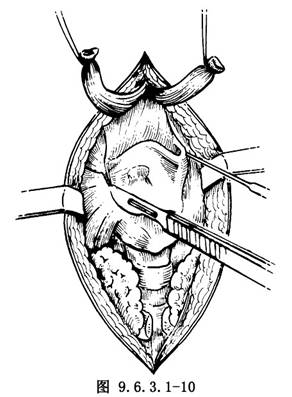

(4)鬆動喉體:先於甲狀舌骨膜兩外側甲狀軟骨上角上方,分出喉上動、靜脈並結紮切斷(圖9.6.3.1-9),同時切斷喉上神經,用骨剪剪斷甲狀軟骨上角,沿甲狀軟骨翼板後緣切斷嚥下縮肌(圖9.6.3.1-10)。此時應注意結紮甲狀腺上動脈的環甲支,然後將梨狀窩黏膜自甲狀軟骨翼板後內側面分離。再沿甲狀軟骨板後下緣向下切斷甲狀軟骨下角。